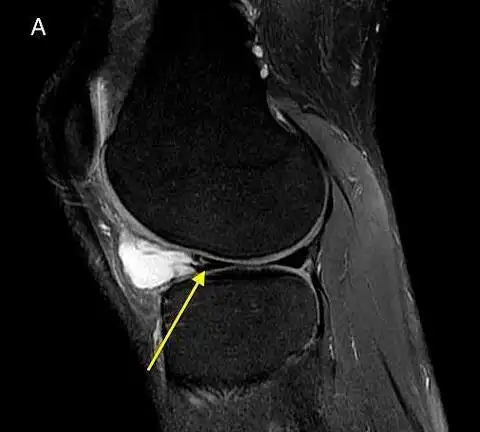

关节镜下半月板囊肿清理一例

王先生经膝关节磁共振检查后提示:右膝内侧半月板后角撕裂,半月板囊肿